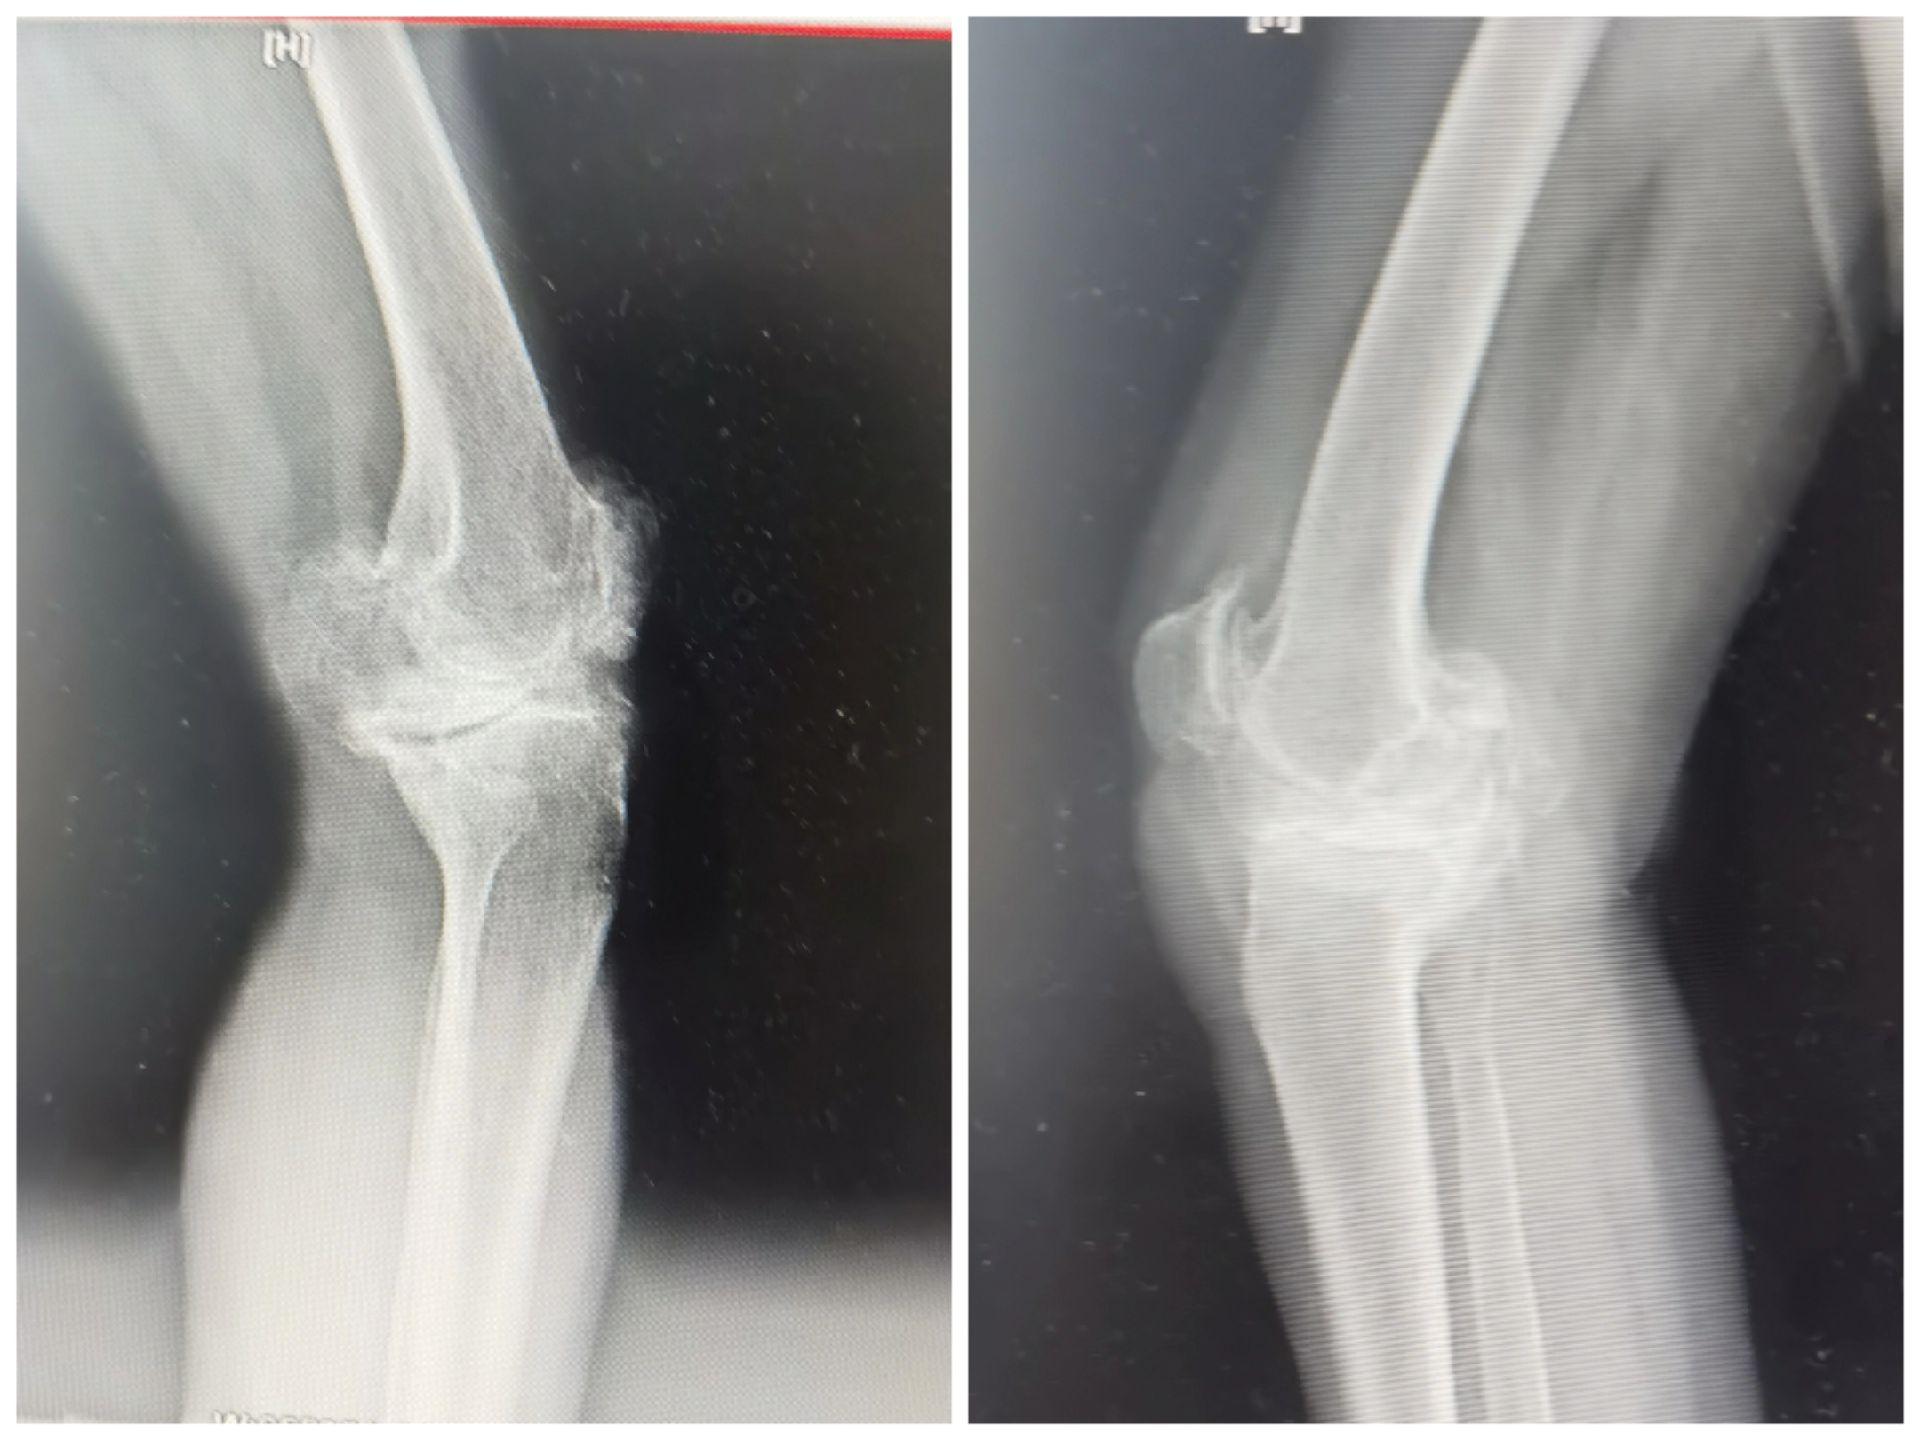

膝关节置换TKA.骨关节炎重度内翻合并屈曲挛缩畸形,无法行走,一期行双侧TKA,愿每一位患者都能得到有效的治疗,都能早日恢复正常生活🌹